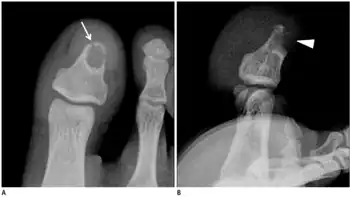

a,b) Male with desmoplastic fibroma in first toe